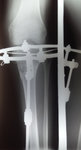

Рентген в 81 день с момента операции.

Здравствуйте, Соломея! По рентгену, у Вас всё отлично! В 90 дней возможно снятие аппаратов. Натаптывайте интенсивно ножки все эти дни, но без фанатизма(ведь когда я Вам говорю больше ходите- это значит, что при физ нагрузке быстрее разрастается костная ткань - вырабатывается, наступает сращение) лучше приехать и остаться у нас в клинике до снятия аппаратов. Один раз можно пожертвовать временем, расстоянием и средствами ради благополучия и отличного результата! Ножки мы исправляем один раз и навсегда!